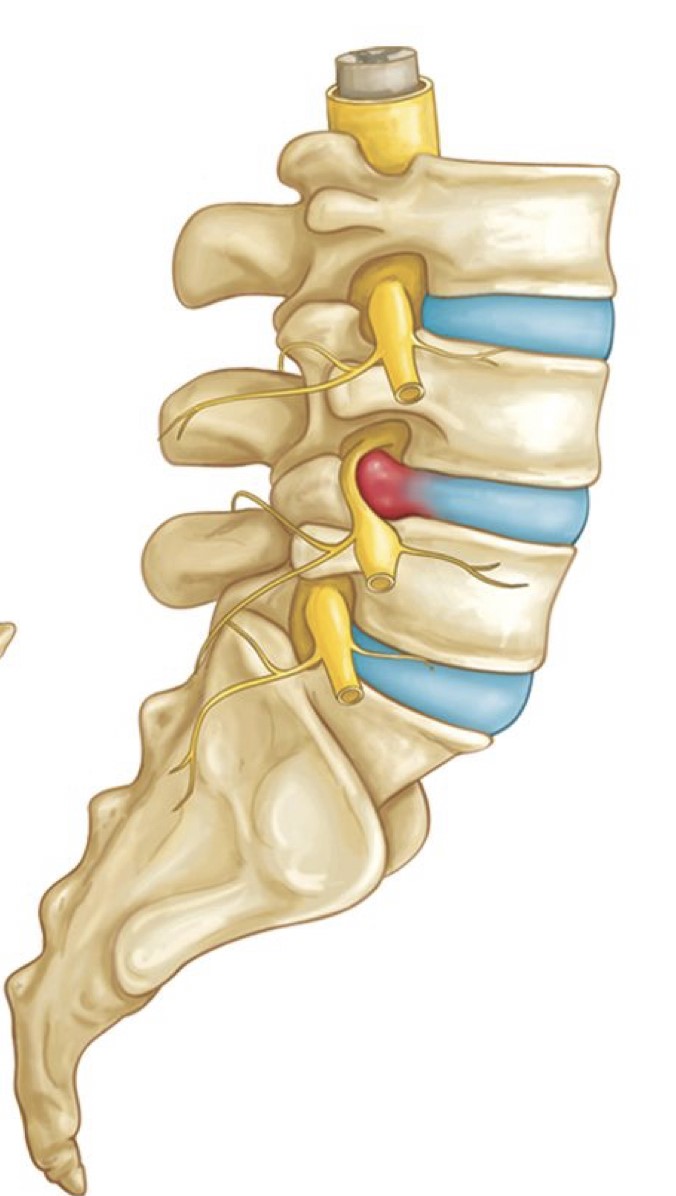

Fractured spine

Fractured spine 140 фотографий